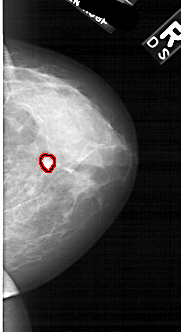

A_1877_1.LEFT_MLO

LEFT_MLO LINES 6481 PIXELS_PER_LINE 3061 BITS_PER_PIXEL 12 RESOLUTION 43.5 NON_OVERLAY

FILE: A_1877_1.RIGHT_MLO.OVERLAY

TOTAL_ABNORMALITIES 1

ABNORMALITY 1

LESION_TYPE MASS SHAPE LOBULATED MARGINS CIRCUMSCRIBED

ASSESSMENT 4

SUBTLETY 3

PATHOLOGY BENIGN

TOTAL_OUTLINES 1

BOUNDARY